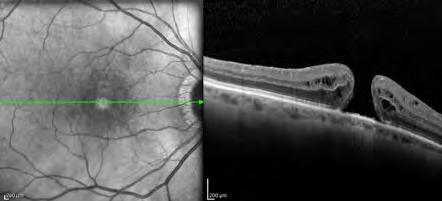

ordine (Coma e vertical trefoil), l’elevazione posteriore (PE) misurate utilizzando il Tomografo Precisio 2 ed il tomografo Sirius. È stato inoltre eseguito l'OCT corneale del segmento anteriore (OptoVue, Freemont, Irvine, CA, USA) per valutare la linea di demarcazione (DL) e lo spessore minimo corneale (MCT). Tutti i pazienti inclusi nello studio avevano completato il follow-up di 48 mesi.

Una linea di demarcazione è stata documentata durante il primo mese di valutazione postoperatoria utilizzando l'OCT del segmento anteriore in tutti i casi osservati. La linea di demarcazione media era ad una profondità media di 238,2 ± 33 µm.